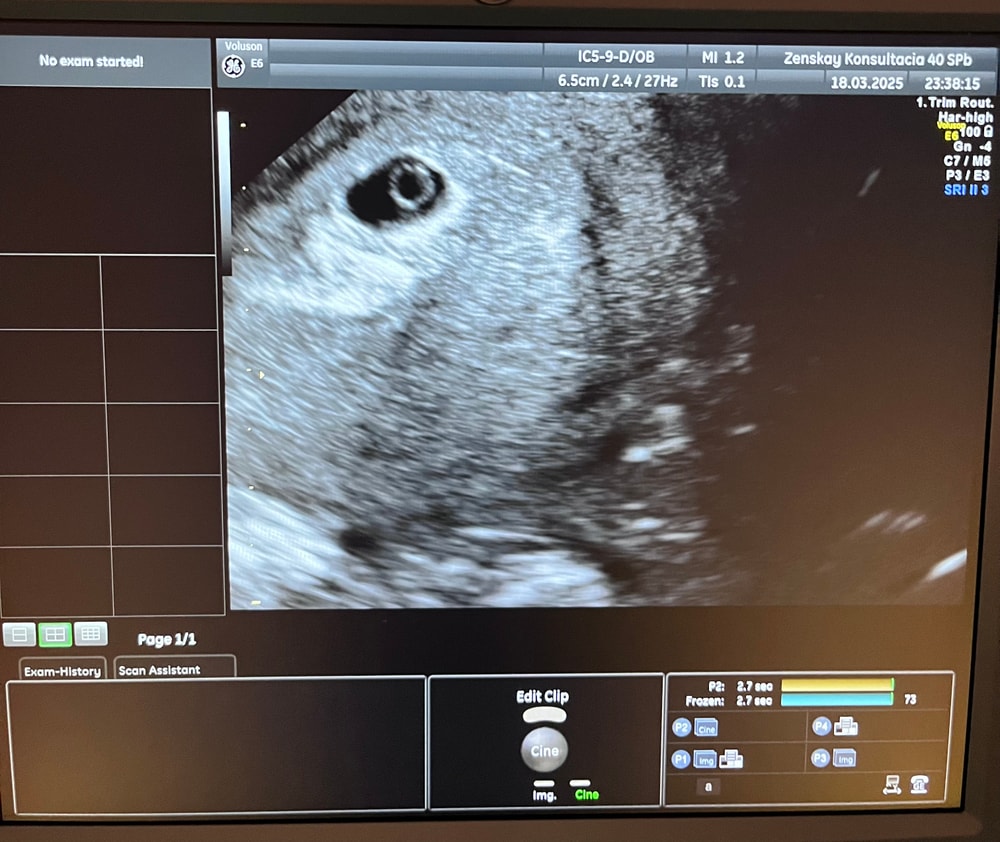

Результаты УЗИВчера был 21 дпп, и было первое узи😊

И вот, лежу я на кушетке, врач вводит датчик и сердце мое замерло! Так как до этого недели 2 тянуло низ живота, и это была не матка, а хрен пойми что, собственно из-за этого и все нервы😁 Я уже себе навыдумывала и внематочную, замершую и все самое плохое. И она начинает говорить что плодное яйцо в полости матки, даже есть желточный мешочек, сообщает размеры, эмбриончика еще не видно, но он есть. Думаю это из-за аппарата узи, так как в нашей гинекологии он не новый.